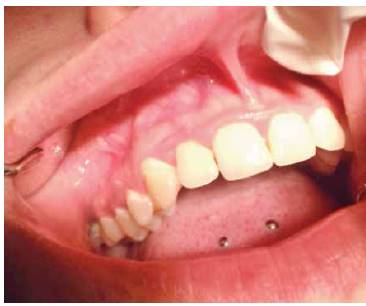

Al realizar el examen intraoral se observa un aumento de volumen de forma ovalada que va desde el margen gingival, abarcando encía adherida hasta muy cerca del fondo de vestíbulo. Esta lesión se extiende desde distal del diente 1.1 hasta mesial del 1.4. A la palpación, su consistencia es muy firme y tiene un color rosa pálido y presenta una base pediculada (Figura 1 y 2).

Se observa higiene oral deficiente y lesiones activas cervicales en dientes anteriosuperiores.